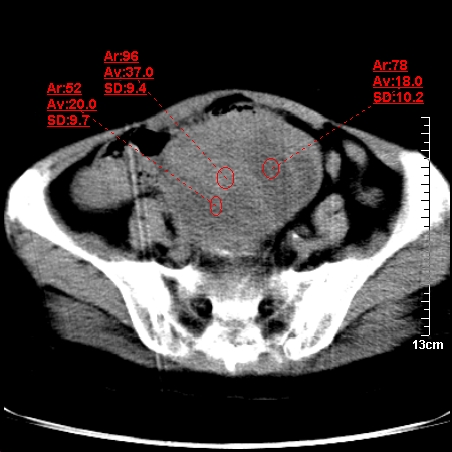

术前的疏忽,手术前诊断阑尾炎,但是没有常规做b超,导致术后1周检查发现 1。实性包块?2。腹腔术后脓肿?

病史:病人一周前诊断阑尾炎,未做b超,手术发现阑尾化脓,(没有留意有无包块),术后1周病人发热,血象:1.6万,做b超发现,随ct检查,上传图片

巨大囊实性包块,边界大部尚清楚,不太像脓肿的表现。应该做个增强检查除外盆腔肿瘤。

脓肿可能性大. 因回盲部区域化脓性兰尾切除残端感染改变征像与实性肿块关系密切.肿块上界至右下腹,下界至盆腔膀胱上缘, 如果是实性肿块在兰尾术中可能就会发现. 所以术后一周病人高烧, 白细胞增高,临床表现支持脓肿.

盆腔一边界大部份清晰囊实性肿块,其周腹脂未见确切异常,其一端与右侧附件相连。考虑右侧附件肿瘤。

如果能进行肠道准备就好了!盆腔内巨大囊实性包块,右前缘与周围肠管分界不清,病灶内前部的气体是否为肠管内气体形成的假象不能确定。

这么大一包快手术当中没有发现?值得怀疑!结合化脓性阑尾炎病史,首先考虑脓肿!不排外附件来源的肿瘤,建议增强扫描!!